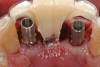

Preoperatively, 1 g of amoxicillin was administered. Using local anesthesia (lidocaine 1:100,000 epinephrine), extractions of teeth No. 23 to No. 26 were performed without raising a flap and with gentle luxation to preserve the remaining facial osseous plate. The sockets were curetted prior to implant placement. A vacuum-formed surgical guide, fabricated based on a diagnostic wax-up of the desired tooth positions for the subsequent fixed prosthesis, was used during implant placement. Osteotomies were performed at sites No. 23 and No. 26 and positioned toward the lingual aspects of the sockets (Figure 3A and Figure 3B). Two tapered implants (OsseoTite™ 313, BIOMET 3i™, Palm Beach Gardens, FL) measuring 3.25 mm x 13 mm were placed. Conical prosthetic abutments (3-mm height) were used to facilitate joining the two implants in a screw-retained fixed partial denture (Figure 4). A laboratory-processed acrylic-resin provisional restoration was altered to allow connection to the temporary cylinders. The provisional was placed into the vacuum-formed surgical guide that was now used to maintain the provisional in the correct 3-dimensional position (Figure 5) while being attached to the temporary cylinders with acrylic resin intraorally. Once a sufficient amount of acrylic resin was placed to secure the cylinders to the provisional, it was removed from the mouth and its contours were completed at the laboratory bench (Figure 6A). The two central incisor sockets were grafted with small-particle allograft material (Puros® Allograft, Zimmer Dental, Carlsbad, CA) to maintain gingival architecture beneath two ovate pontics (Figure 6B). The provisional restoration was inserted and the screws tightened to 20 Nt-cm of torque.